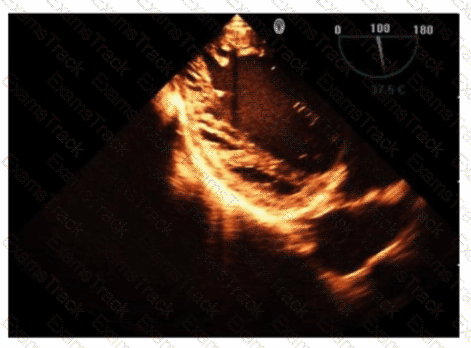

Which is the most likely abnormality represented in these images from a 48-year-old man with shortness of breath?